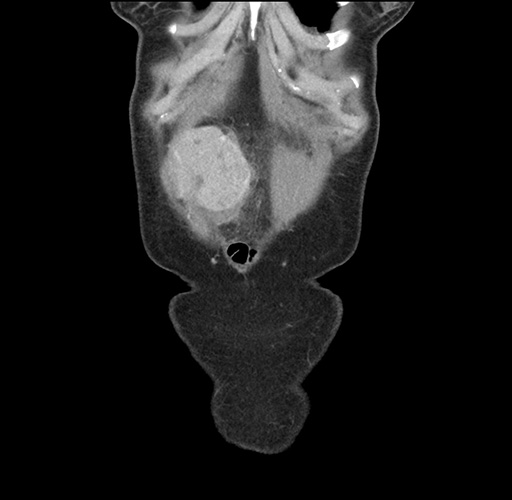

Imaging Analysis

Look through the patient's CT scan to identify any areas of concern for the necessary procedure.

Based on your CT findings, which issue(s) would give reason for "planned slowing down moment(s)" in this case?

Considering a standard left lateral sectionectomy procedure, what step(s) of the operation would you do differently in this case ?